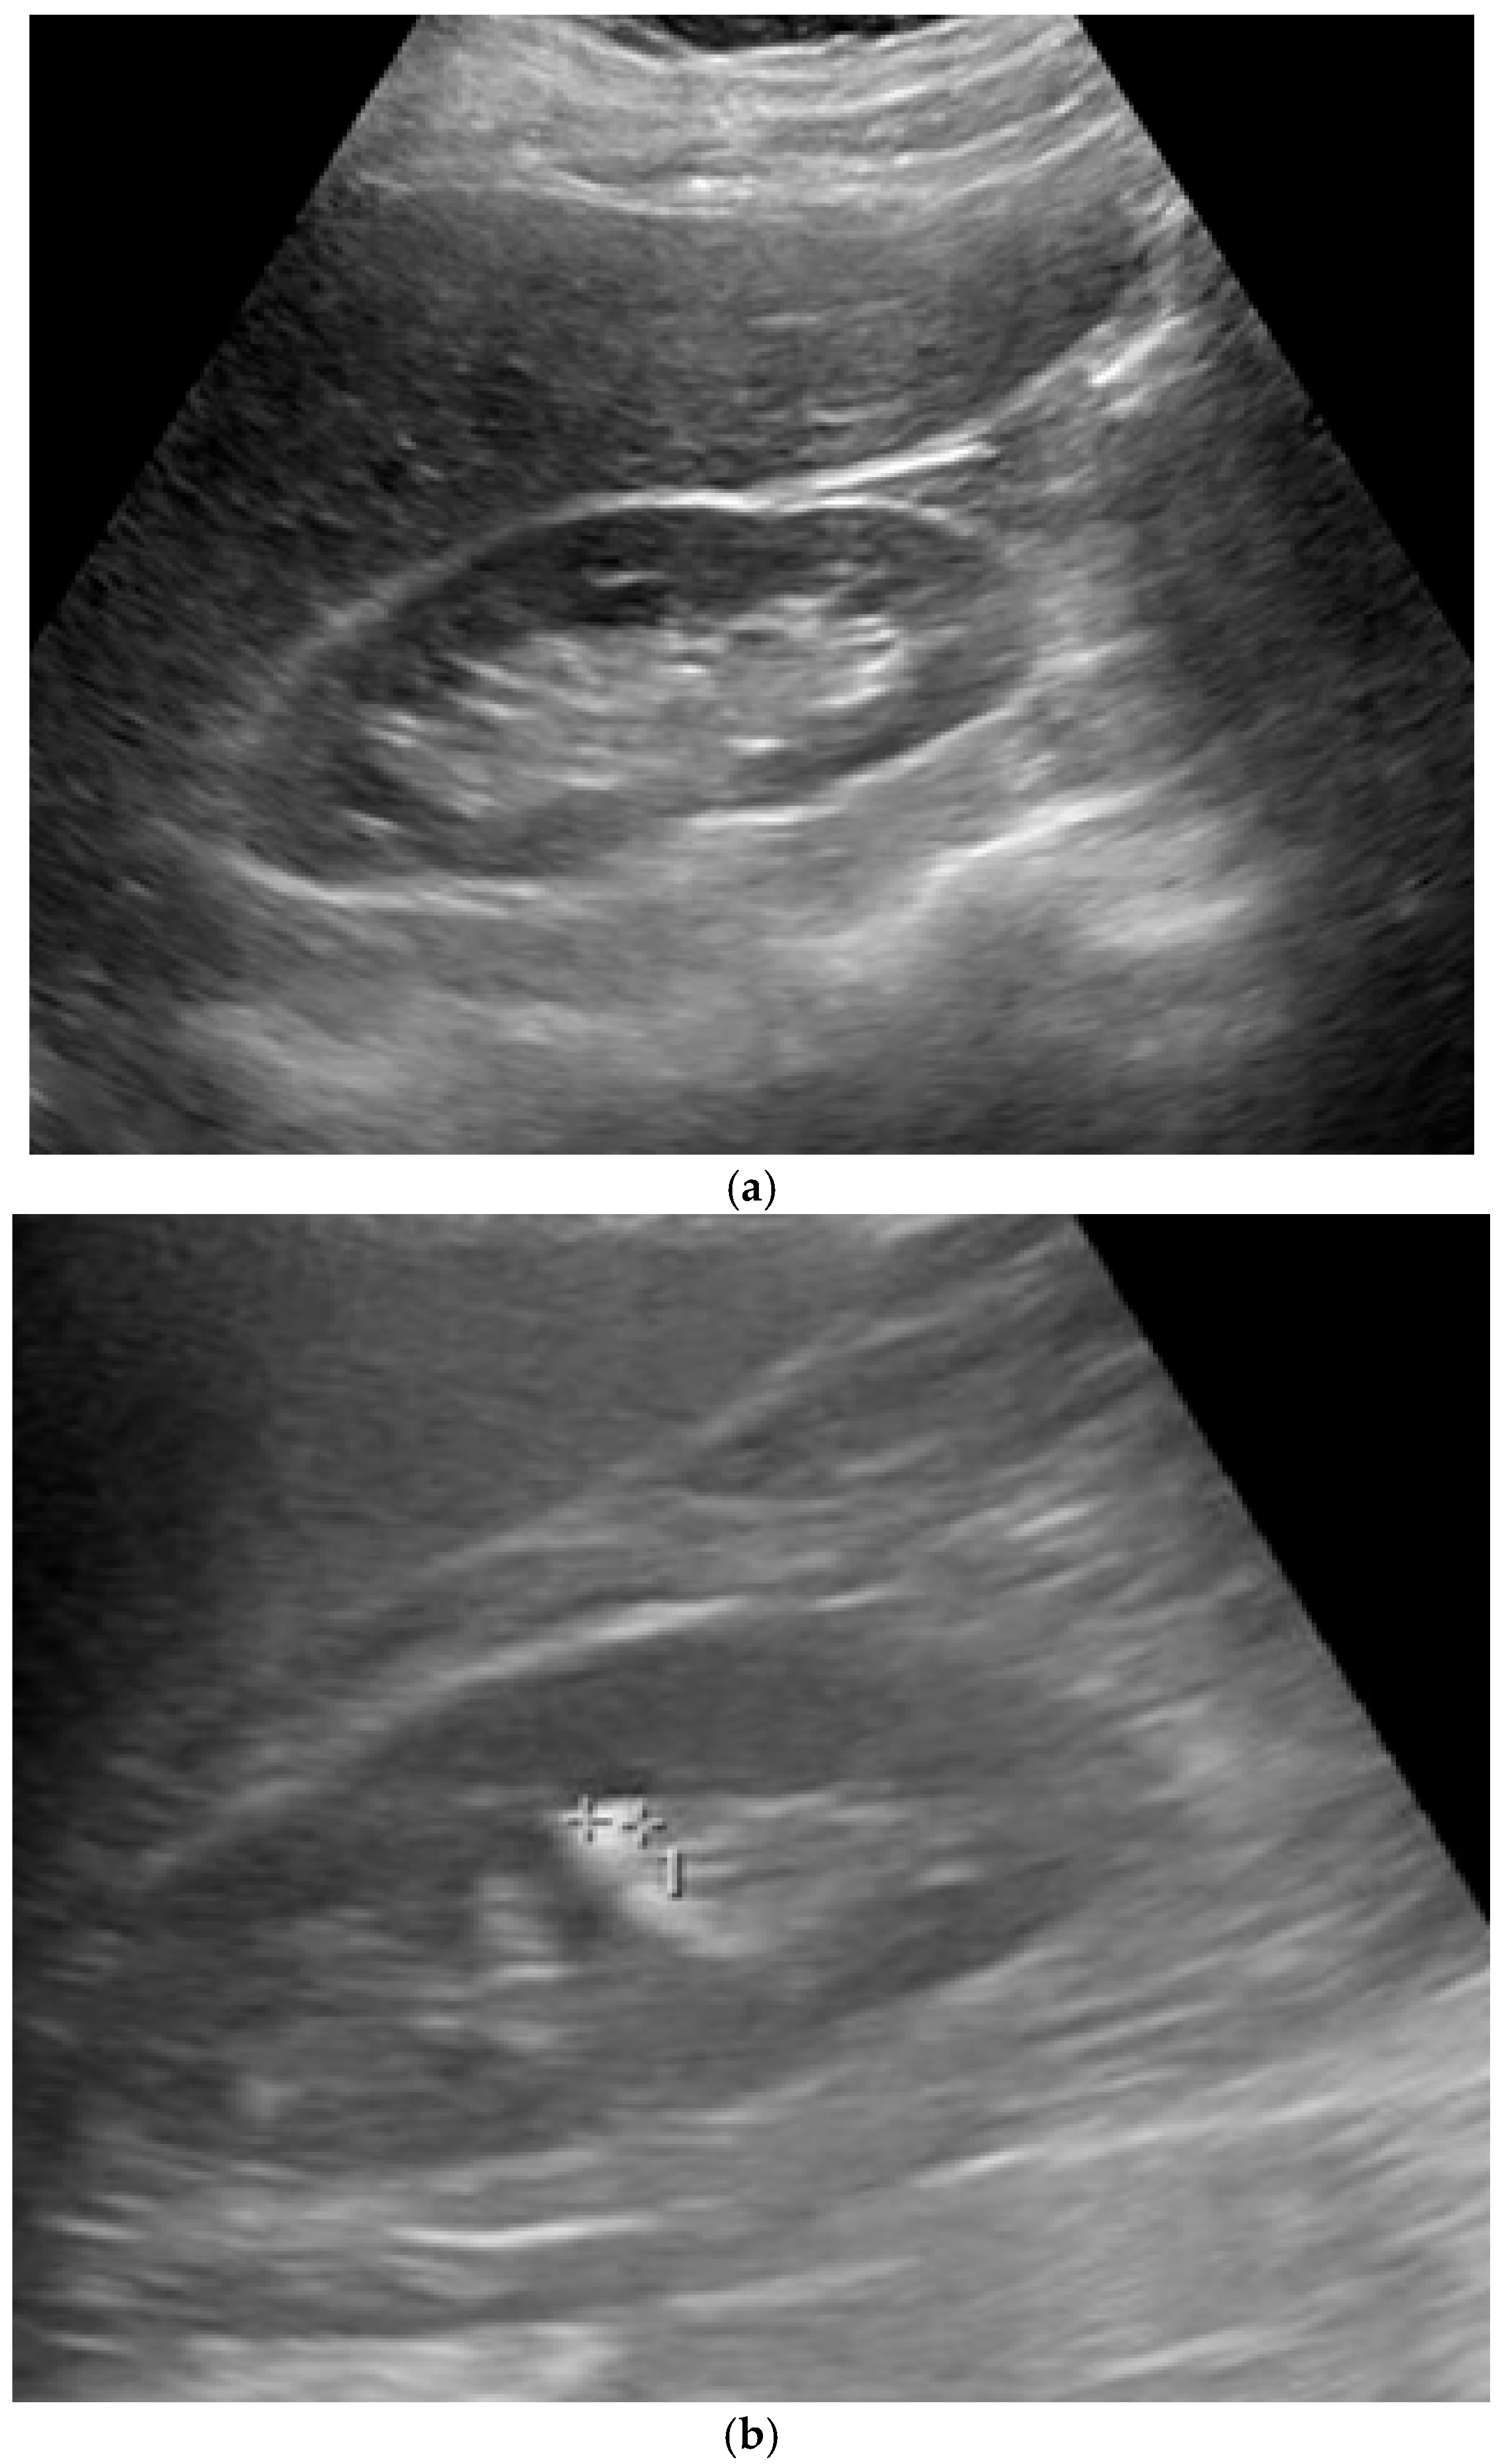

Figure 1. Ultrasound images: (a) normal kidney, (b) kidney with stones and visible caliper markers (++1) that are used for measuring the dimensions of the stone (++ for width and 1 for height/thickness).